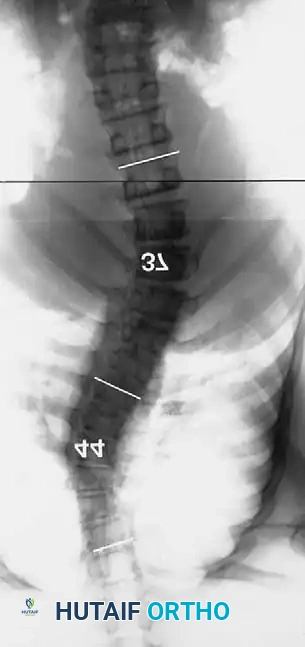

Dystrophic scoliosis is the most aggressive and challenging variant. It is characterized by a short-segment, sharply angulated curve. Radiographically, dystrophic curves present with a constellation of severe structural anomalies:

* Severe wedging of the apical vertebral bodies.

* Extreme axial rotation of the vertebrae.

* Posterior scalloping of the vertebral bodies (often secondary to dural ectasia).

* Spindling (thinning) of the transverse processes.

* Enlargement of the neural foramina.

* "Penciled ribs": Rotation of the ribs 90 degrees in the anteroposterior direction, making them appear abnormally thin and dysplastic.

Curves with significant sagittal plane deformity are highly prevalent in dystrophic scoliosis. Neurofibromatosis kyphoscoliosis is particularly notorious, characterized by acute, rigid angulation in the sagittal plane and striking destruction or deformity of the vertebral bodies near the apex. Severe thoracic lordoscoliosis has also been documented by Winter, presenting unique respiratory and biomechanical challenges.

Dystrophic Kyphoscoliosis

Dystrophic scoliosis coupled with angular kyphosis represents one of the most formidable challenges in spine surgery. Patients with this pathology respond exceptionally poorly to posterior fusion alone. Consistent, long-term success is achieved almost exclusively through combined anterior and posterior (360-degree) fusions.

Fig. 38-202: Postoperative radiographs demonstrating anterior fusion with vascularized rib graft and structural strut grafting in a patient with severe dystrophic kyphoscoliosis.